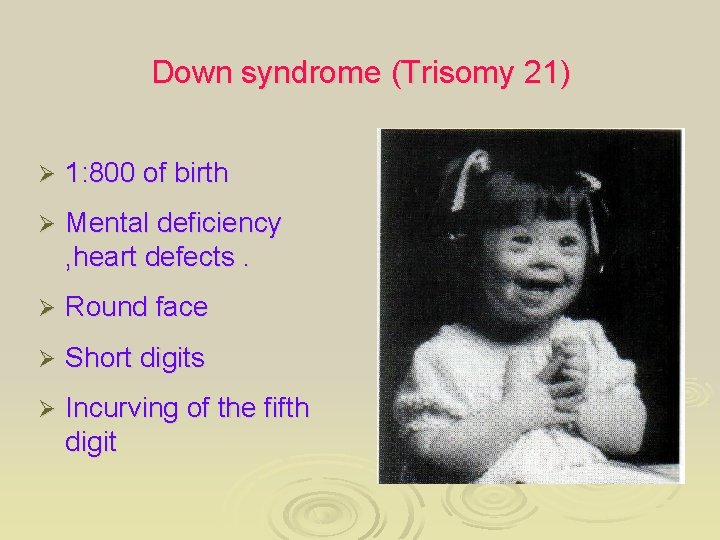

Down syndrome (Trisomy 21) Ø 1: 800 of birth Ø Mental deficiency , heart defects. Ø Round face Ø Short digits Ø Incurving of the fifth digit